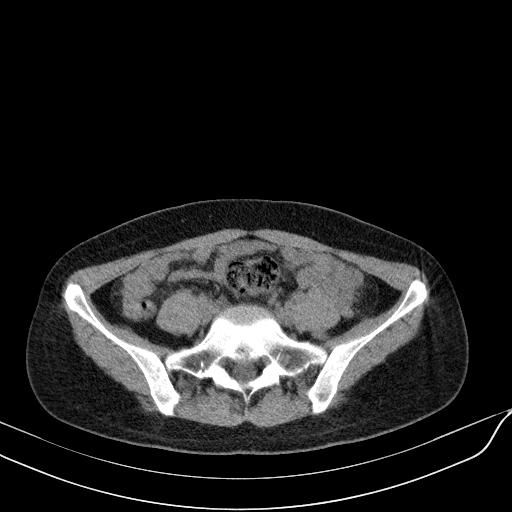

标题: CT23965:无外伤史,下腹痛 [打印本页]

标题: CT23965:无外伤史,下腹痛

肠道未准备,继续往下扫,乙状结肠占位不排除。建议钡灌或结肠镜检查。

乙状结肠占位不排除

未见明显异常改变,做个气钡双重造影除外一下结肠病变,无外伤史为啥不常规喝泛影葡胺水对比剂再扫ct呢?

肠道肿瘤,建议行钡剂灌肠检查。